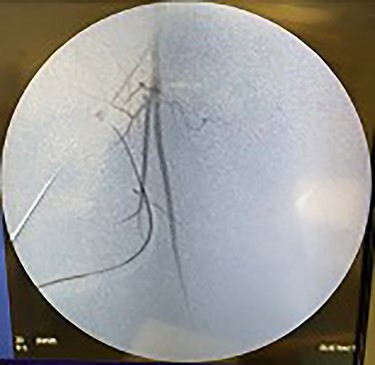

Fluoroscopy of bilateral iliac arteries showing significant arterial disease.